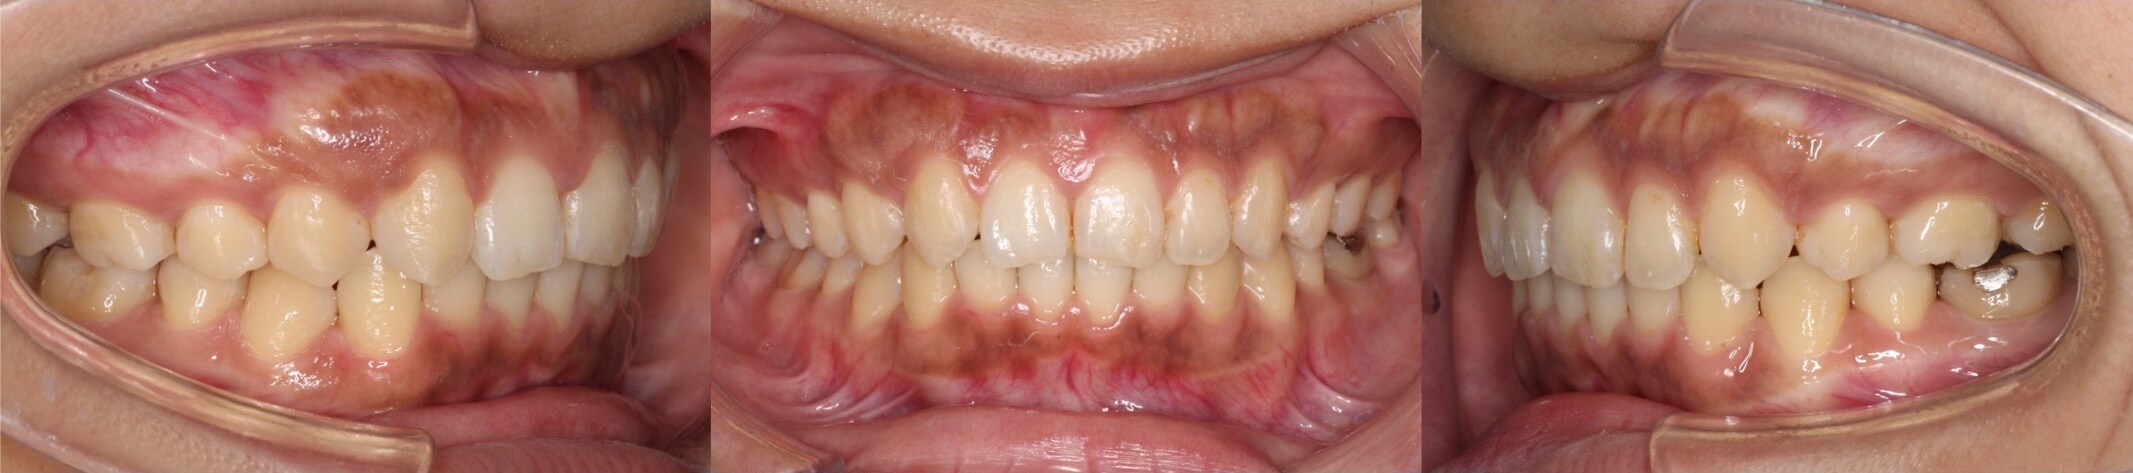

20代女性・先天性欠損2歯・下5欠損

前歯を後ろに倒し込まないように注意しながら、顎間ゴムを使って下の奥歯を前方移動して下の欠損スペースを閉鎖しました。上の抜歯部位は、左右の非対称にすることでうまく正中線を合わせました。下5番抜歯空隙の閉鎖は、後ろにある6番の歯根の移動量が多く治療期間が長くなりやすいです。

<症例概要> 難易度★★★★☆

主訴:下の欠損歯の空隙

年齢・性別:20代女性

症状:左右下5番欠損・空隙・右7シザーズバイト・下顎左偏

治療方針:上顎歯列拡大・下顎臼歯近心移動・

抜歯:右上5番・左上4番

固定装置:アーム付きリンガルアーチ・圧下アーチ・II級ゴム

治療装置:唇側矯正装置

治療期間:2年10か月

リテーナー:上下プレートタイプ

治療費用:990,000(税込)

代表的副作用:痛み・治療後の後戻り・歯根吸収・歯髄壊死・歯肉退縮